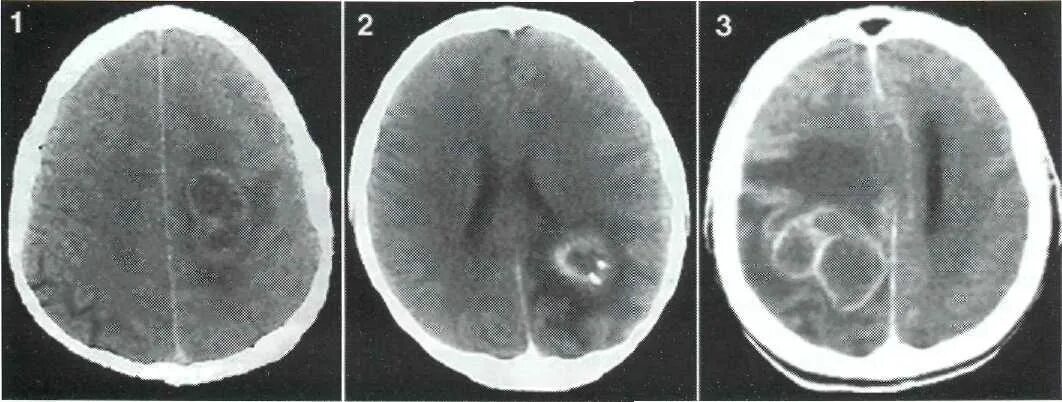

Метастазы головного мозга кт